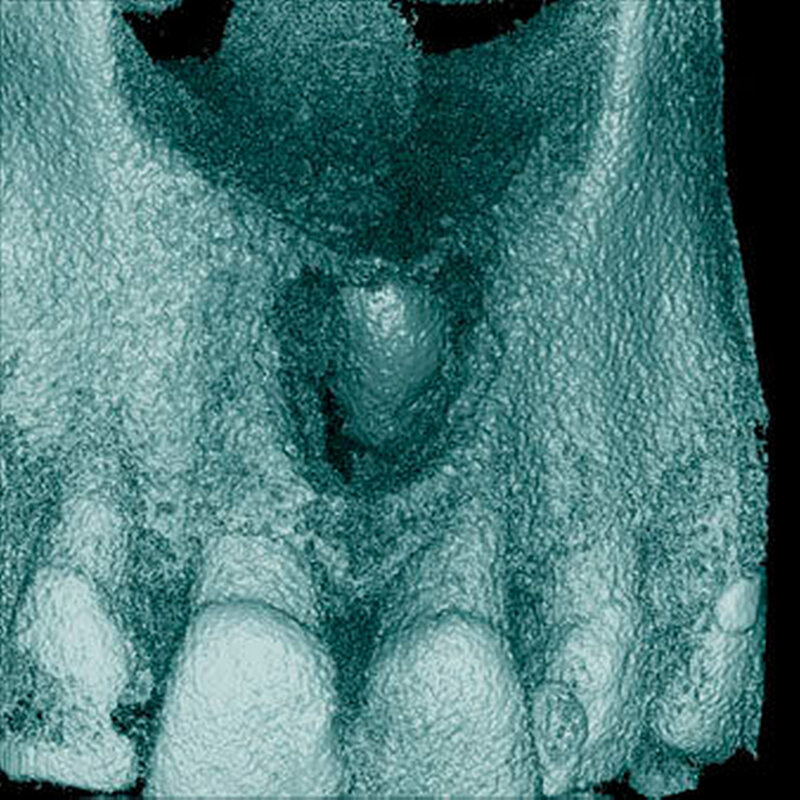

In einer aktuellen Arbeit berichteten Mossaz und Mitarbeiter (2014) über eine relativ hohe Prävalenz (22,8 Prozent) der Wurzel- resorptionen an benachbarten Zähnen, wobei besonders häufig überzählige Prämolaren zu Resorptionen führen (Abbildung 18). Für die Beurteilung der Wurzelresorptionen wurden digitale Volumentomografie (DVT) der Patienten herangezogen. In einer Studie aus China, welche ebenfalls DVT-Bilder beurteilte, wurde über eine deutlich geringere Häufigkeit von Wurzelresorptionen (1,6 Prozent) berichtet [Liu et al., 2007]. Im Gegensatz zu den Daten aus der Schweiz war Diagnose und Bewertung von Wurzelresorptionen kein primäres Ziel dieser Studie und es wurde auch keine Information über das Ausmaß der Resorptionen gegeben.

Daher könnte diese Studie leichte oder mäßige Wurzelresorptionen nicht eingeschlossen haben, was zumindest einen Teil des doch deutlichen Unterschieds in den Prozentsätzen erklären würde. Studien, welche Panoramaschichtaufnahmen zur Diagnose von Wurzelresorptionen heranziehen, berichten über Resorptionsraten zwischen 4,7 Prozent [Gündüz et al., 2008] und 7,6 Prozent [Hyun et al., 2009]. Tyrologou und Mitarbeiter (2005) berichteten sogar, dass keine Resorption im untersuchten Patientengut vorhanden waren. Allerdings wurden in dieser Studien nur Mesiodentes beurteilt, wo Wurzelresorption benachbarter Zähne eher selten vorkommen [Mossaz et al., 2014]. Generell lässt sich festhalten, dass zweidimensionale Röntgenaufnahmen für die Diagnose von Wurzelresorptionen eher ungenau sind und diese so in bis zu 50 Prozent der Fälle übersehen werden [Ericson Kurol, 1987, Heimisdottir et al., 2005; Botticelli et al., 2011; Alqerban et al., 2011a].